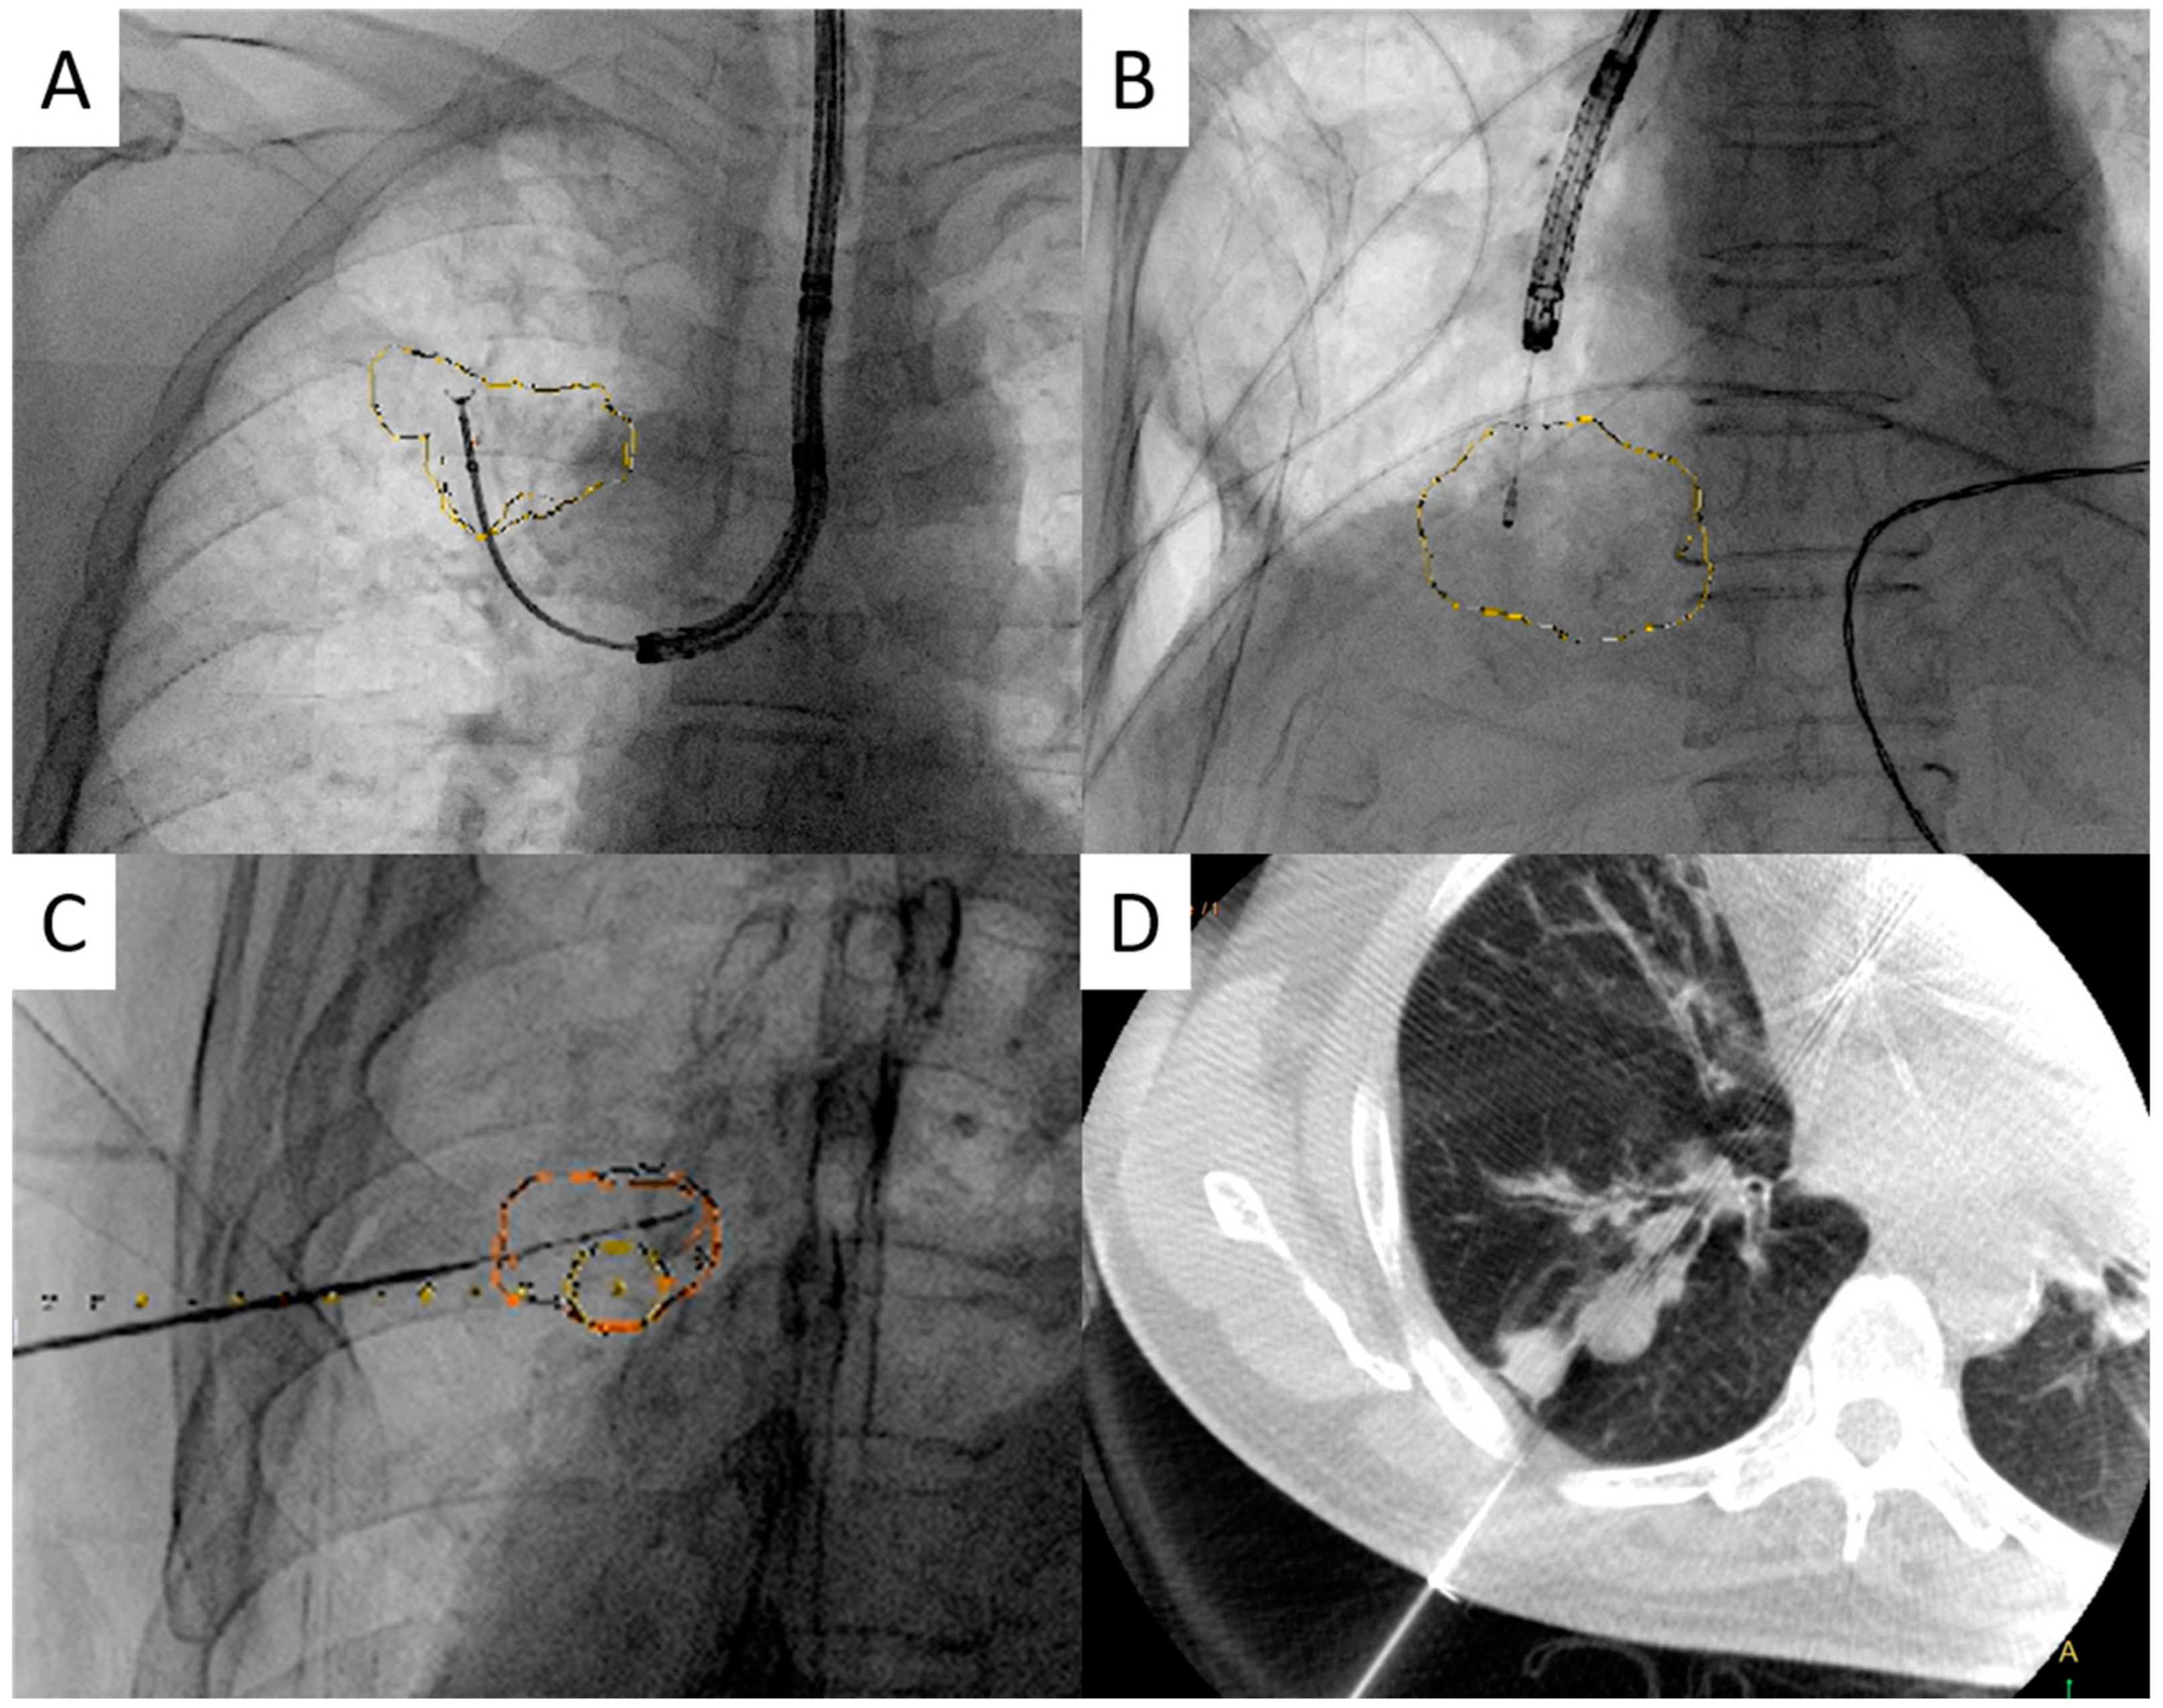

Cone-Beam Computed-Tomography-Derived Augmented Fluoroscopy-Guided Biopsy for Peripheral Pulmonary Nodules in a Hybrid Operating Room: A Case Series

2.2. Procedures